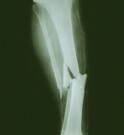

SSRIs Tied to Higher Fracture Odds in Menopausal Women

Risk remains high over several years